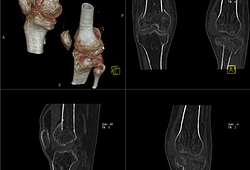

>> RESONANCIA MAGNÉTICA >> TOMOGRAFÍA

Brindamos el servicio de lectura

La lectura  de estudios radiológicos de urgencia se realiza en un lapso de 30 minutos, según la complejidad del caso ,  mientras que la lectura de estudios de rutina se realizan dentro de las 24 a 48 horas de recibido el examen.